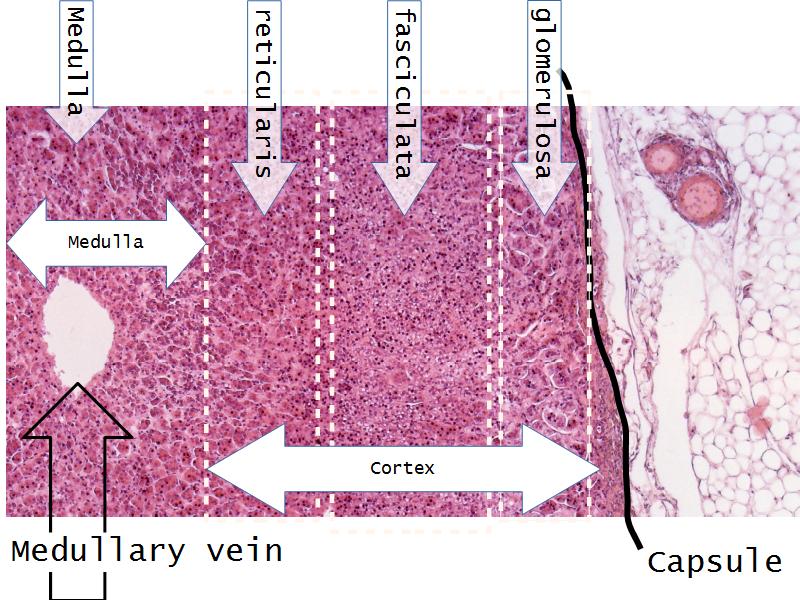

- Slide 56: Adrenal glands

Adrenal glands

Capsule

Cortex - how many zones?

Medulla

Hormones of each?